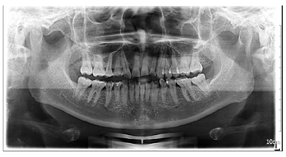

曲线不平(图2,图3)。(4)影像学检查:

曲面体层片示双侧下颌骨未见明显不对称,牙槽骨未见明显吸收;44牙

面充填物,未见根充物,根尖无明显异常(图4)。CBCT示:双侧髁突形态不对称,左侧髁突表面中央凹陷,余骨质未见异常(图5)。